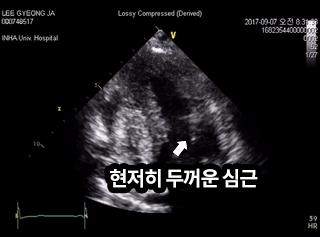

비후성 심근증

비후성 심근증 증례

[비후성 심근증]